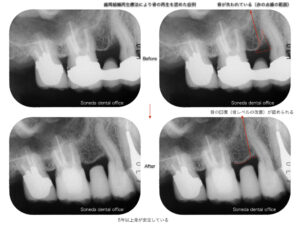

症例2 歯周再生療法を行い骨回復を認めた症例

特定の部位に限局した骨欠損(垂直性骨欠損)が認められた症例では、骨の形態と周囲の骨の残存状態を評価し、歯周組織再生療法の適応と判断しました。

術前は骨が大きく失われていましたが、治療後には骨の回復(骨レベルの回復)が認められています。

また、5年以上の経過においても安定した状態を維持しています。

すべての骨欠損に再生療法が適応となるわけではなく、骨の形態に応じて治療法を選択することが重要です。

症例①と症例②のように、歯周病治療では骨の状態や原因に応じて治療法を選択することが重要です。